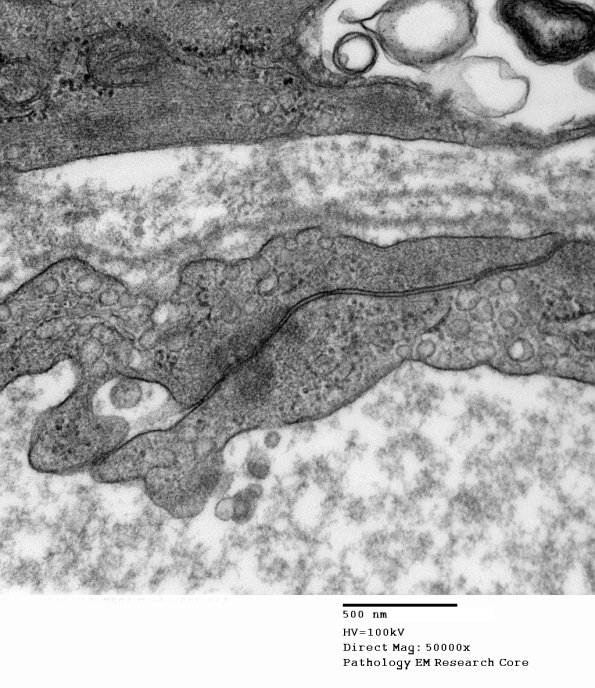

The perineurium as seen at multiple magnifications. The cell to cell junction is well seen in the last image.